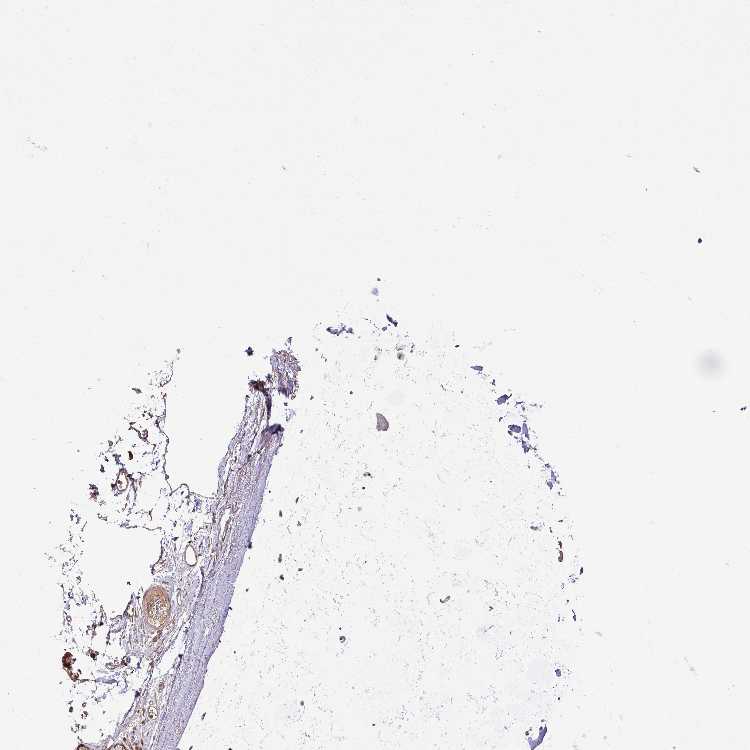

SOFT TISSUE 1 - Antibody stainingi

Antibody staining in the annotated cell types in the current human tissue is reported as not detected, low, medium, or high, based on conventional immunohistochemistry profiling in selected tissues. This score is based on the combination of the staining intensity and fraction of stained cells.

Each image is clickable and will lead to virtual microscopy that enables deeper exploration of all samples and also displays staining intensity scores, fraction scores and subcellular localization as well as patient and tissue information for each sample.

Antibody HPA052488

Fibroblasts Medium

SOFT TISSUE 2 - Antibody stainingi

Peripheral nerve Low